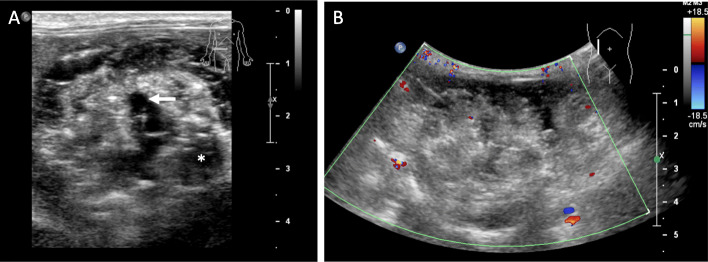

The scout images for the two CT examinations, separated by 5 weeks, showed a large calcified mass that was initially in the left abdomen measured as 5.7 × 3.5 cm (Fig. 1a) and subsequently in the right abdomen measured as 6.5 × 3.8 cm (Fig. 1b). On CT examination, the teratoma measured 6.6 × 4.8 × 4.7 cm and was well-circumscribed, predominantly solid, and heterogenous with soft tissue, fat, and areas of dense calcification (Fig. 1c, d). No fat-fluid levels were identified. Two HCCs were present, one with heterogenous enhancement and necrotic regions. Unlike the enhancement of the HCC after contrast administration, the teratoma did not enhance. The right uterine horn could be traced from the body of the uterus to the mass while the left uterine horn was coiled in the caudal abdomen and pelvis. On ultrasound, the tumor was solid with heterogeneous echogenicity, reflecting the fat content and areas of calcification with acoustic shadowing. Sonolucent areas were present that may have represented cysts. There was little vascularity on color Doppler imaging (Fig. 2). On T1-weighted THRIVE MRI, there was heterogeneously increased signal with areas of signal void representing fat. DWI showed some regions with increased signal. T2-weighted TSE indicated heterogenous hyperintensity while T2-weighted VISTA showed heterogeneous low signal intensity (Fig. 3).

Fig. 2.

Ultrasound. a Grayscale ultrasound. The teratoma was solid with heterogeneous echogenicity, reflecting the fat content and areas of calcification with acoustic shadowing (asterisk) observed. Anechoic areas were present that may have represented cysts (arrow). b. Color Doppler ultrasound. There was little vascularity on color Doppler imaging